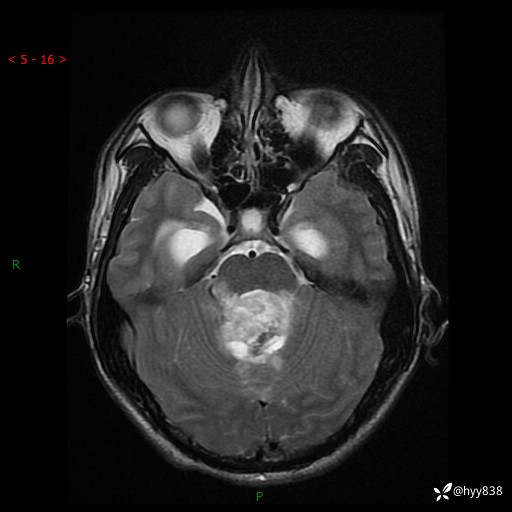

性别:男

年龄:17岁

简要病史:头痛伴间断性呕吐1月余,外院CT提示颅脑占位

颅脑MRI平扫+增强